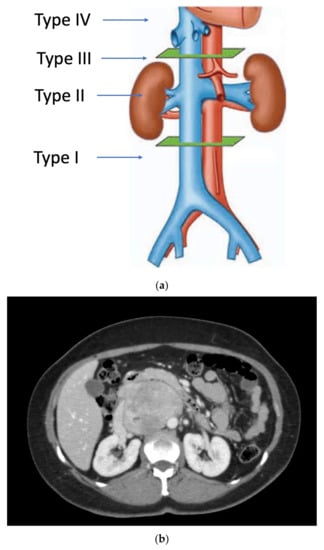

RP-LMSs can also develop from major arterial structures such as the aorta, superior mesenteric artery, or the celiac trunk (Figure 2). Within aortic primary sarcomas, angiosarcomas represent another subset of ultrarare but aggressive tumors with poor outcomes and 5-year survival rates quoted at 8%, portraying a dismal prognosis mostly secondary to metastatic failure or tumor-related complications such as tumor embolization or ostial occlusion, resulting in mesenteric infarction [25].

Spiral CT angiography with 3D reconstruction has become an important tool for surgical planning in tumors originating or infiltrating arterial structures such as the aorta, superior mesenteric artery, celiac trunk, or iliac arteries. The angiography can help to better predict the vascular tissue infiltration versus vascular abutment, whereas the 3D reconstruction can help to determine surrounding organ involvement and accurately plan the type of reconstruction required (Figure 2).

Figure 2. Mesenteric artery LMS: angio-CT and 3D reconstruction.